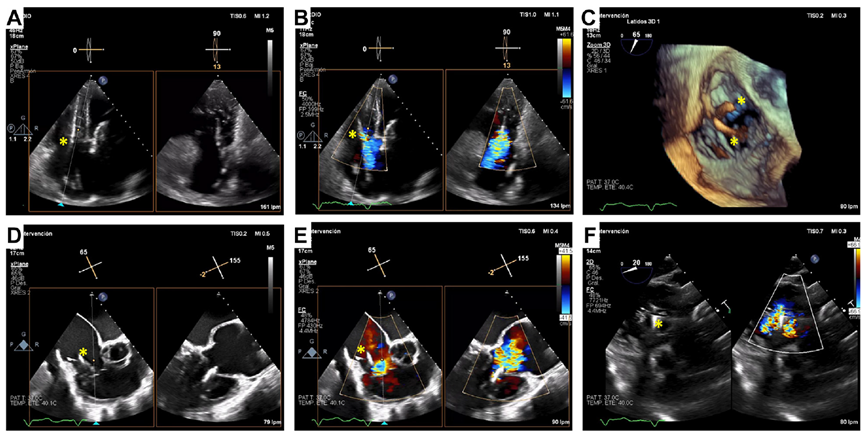

術后經食道超聲,僅微量瓣周漏